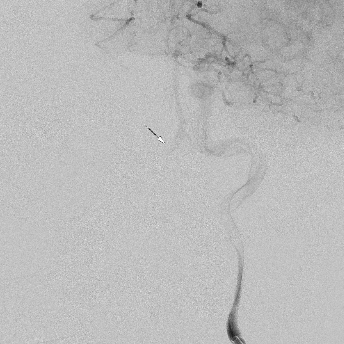

相逢就是缘,有求必全力以赴。立即进行全面评估,CTA和MRI发现颅内多发脑梗塞,脑干为重,双侧椎动脉颅内段基本看不到了,而进一步的DSA造影更为糟糕,左侧椎动脉的颅内颅外段直接全程完全闭塞,右侧颅外剩下一个小尾巴在血液中摇摇欲坠……,诺大的后循环仅仅靠纤细的后交通动脉从前循环借点血液过来,勉强续命,仅仅靠这点前循环的救急,可谓“杯水车薪”,不是“长久之计”,于是决定开通右侧闭塞的椎动脉(颅内+颅外,主要集中在V3+V4段)。

开通这么长节段的夹层所致的椎动脉,说说可以,做起来绝非易事,特别是颅内段,一旦跑到血管外出血,接近脑干,后果严重,谨慎开通的过程还算顺利,微导管带过就是磕磕绊绊不顺利,好吧,小球囊从上到下扩下来,不通,更换稍大球囊扩下来,还是不通,这夹层和狭窄不一样啊,支架导管带过仍然磕磕绊绊,不顺畅,铺开第一个支架,直接来了末端打开不良……,这么长的闭塞段,那得需要多少支架啊?万一放完了,钱花了,不通咋办?

微导管继续超过去,轻轻造影,开通的路径隐约返流闪现,立即改变策略,逆向铺路,开通成功。